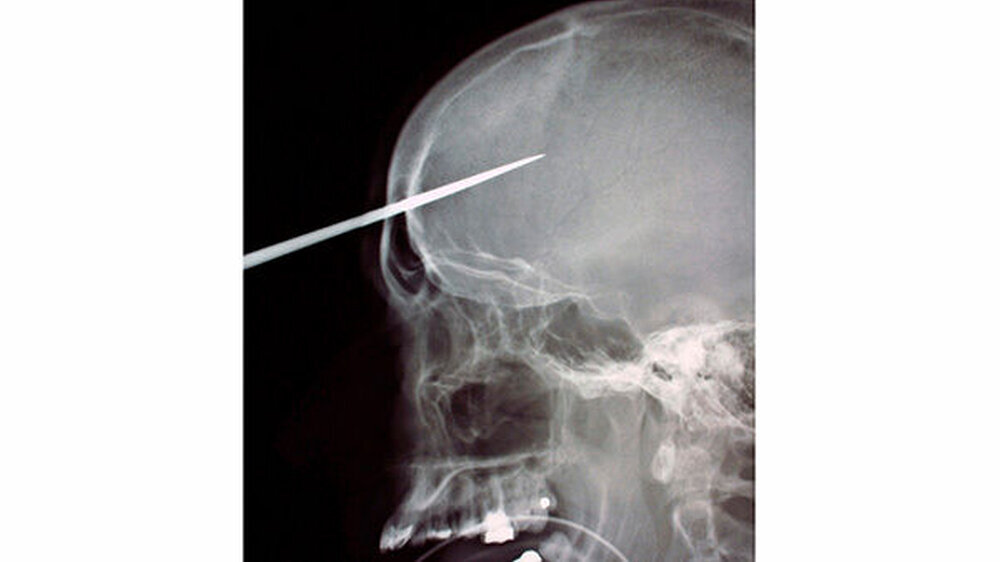

Vom Bohrer im Kopf bis zum Schlüssel in der Kieferhöhle: Die MKG-Chirurgen der Charité haben ausgewählte Patientenfälle mit Fremdkörpern im Gesicht zusammengestellt. In unserer Fotostrecke finden Sie die eindrucksvollen Aufnahmen.